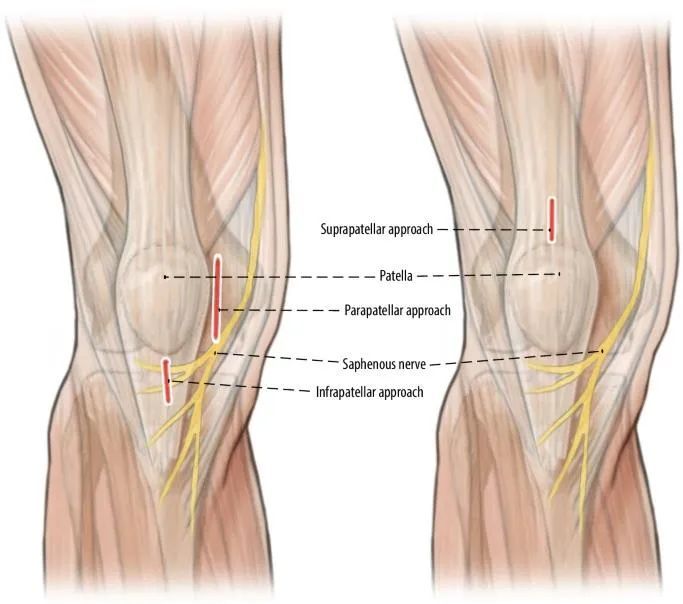

Послеоперационная боль в передней части коленного сустава является актуальной проблемой. Боль в передней части колена наблюдалась у 50–70% пациентов с переломами, и только у 30% пациентов наблюдалось облегчение боли после удаления замыкательной пластинки. По оценкам, образование рубцов на сухожилии надколенника и жировой подушечке Хоффа, связанное с доступом, является потенциальным источником послеоперационной боли в колене. Кроме того, супрапателлярный доступ позволяет избежать традиционного разреза ветви надколенника подкожного нерва, что позволяет избежать онемения передней части колена и притупления чувствительности (рис. 4). Проведение стержня через сухожилие четырехглавой мышцы бедра, оставляя тем самым сухожилие надколенника неповрежденным, значительно снижает частоту послеоперационных болей в колене.

Рис. 4. Соотношение между подкожным нервом и различными доступами к стержню косой большеберцовой мышцы.